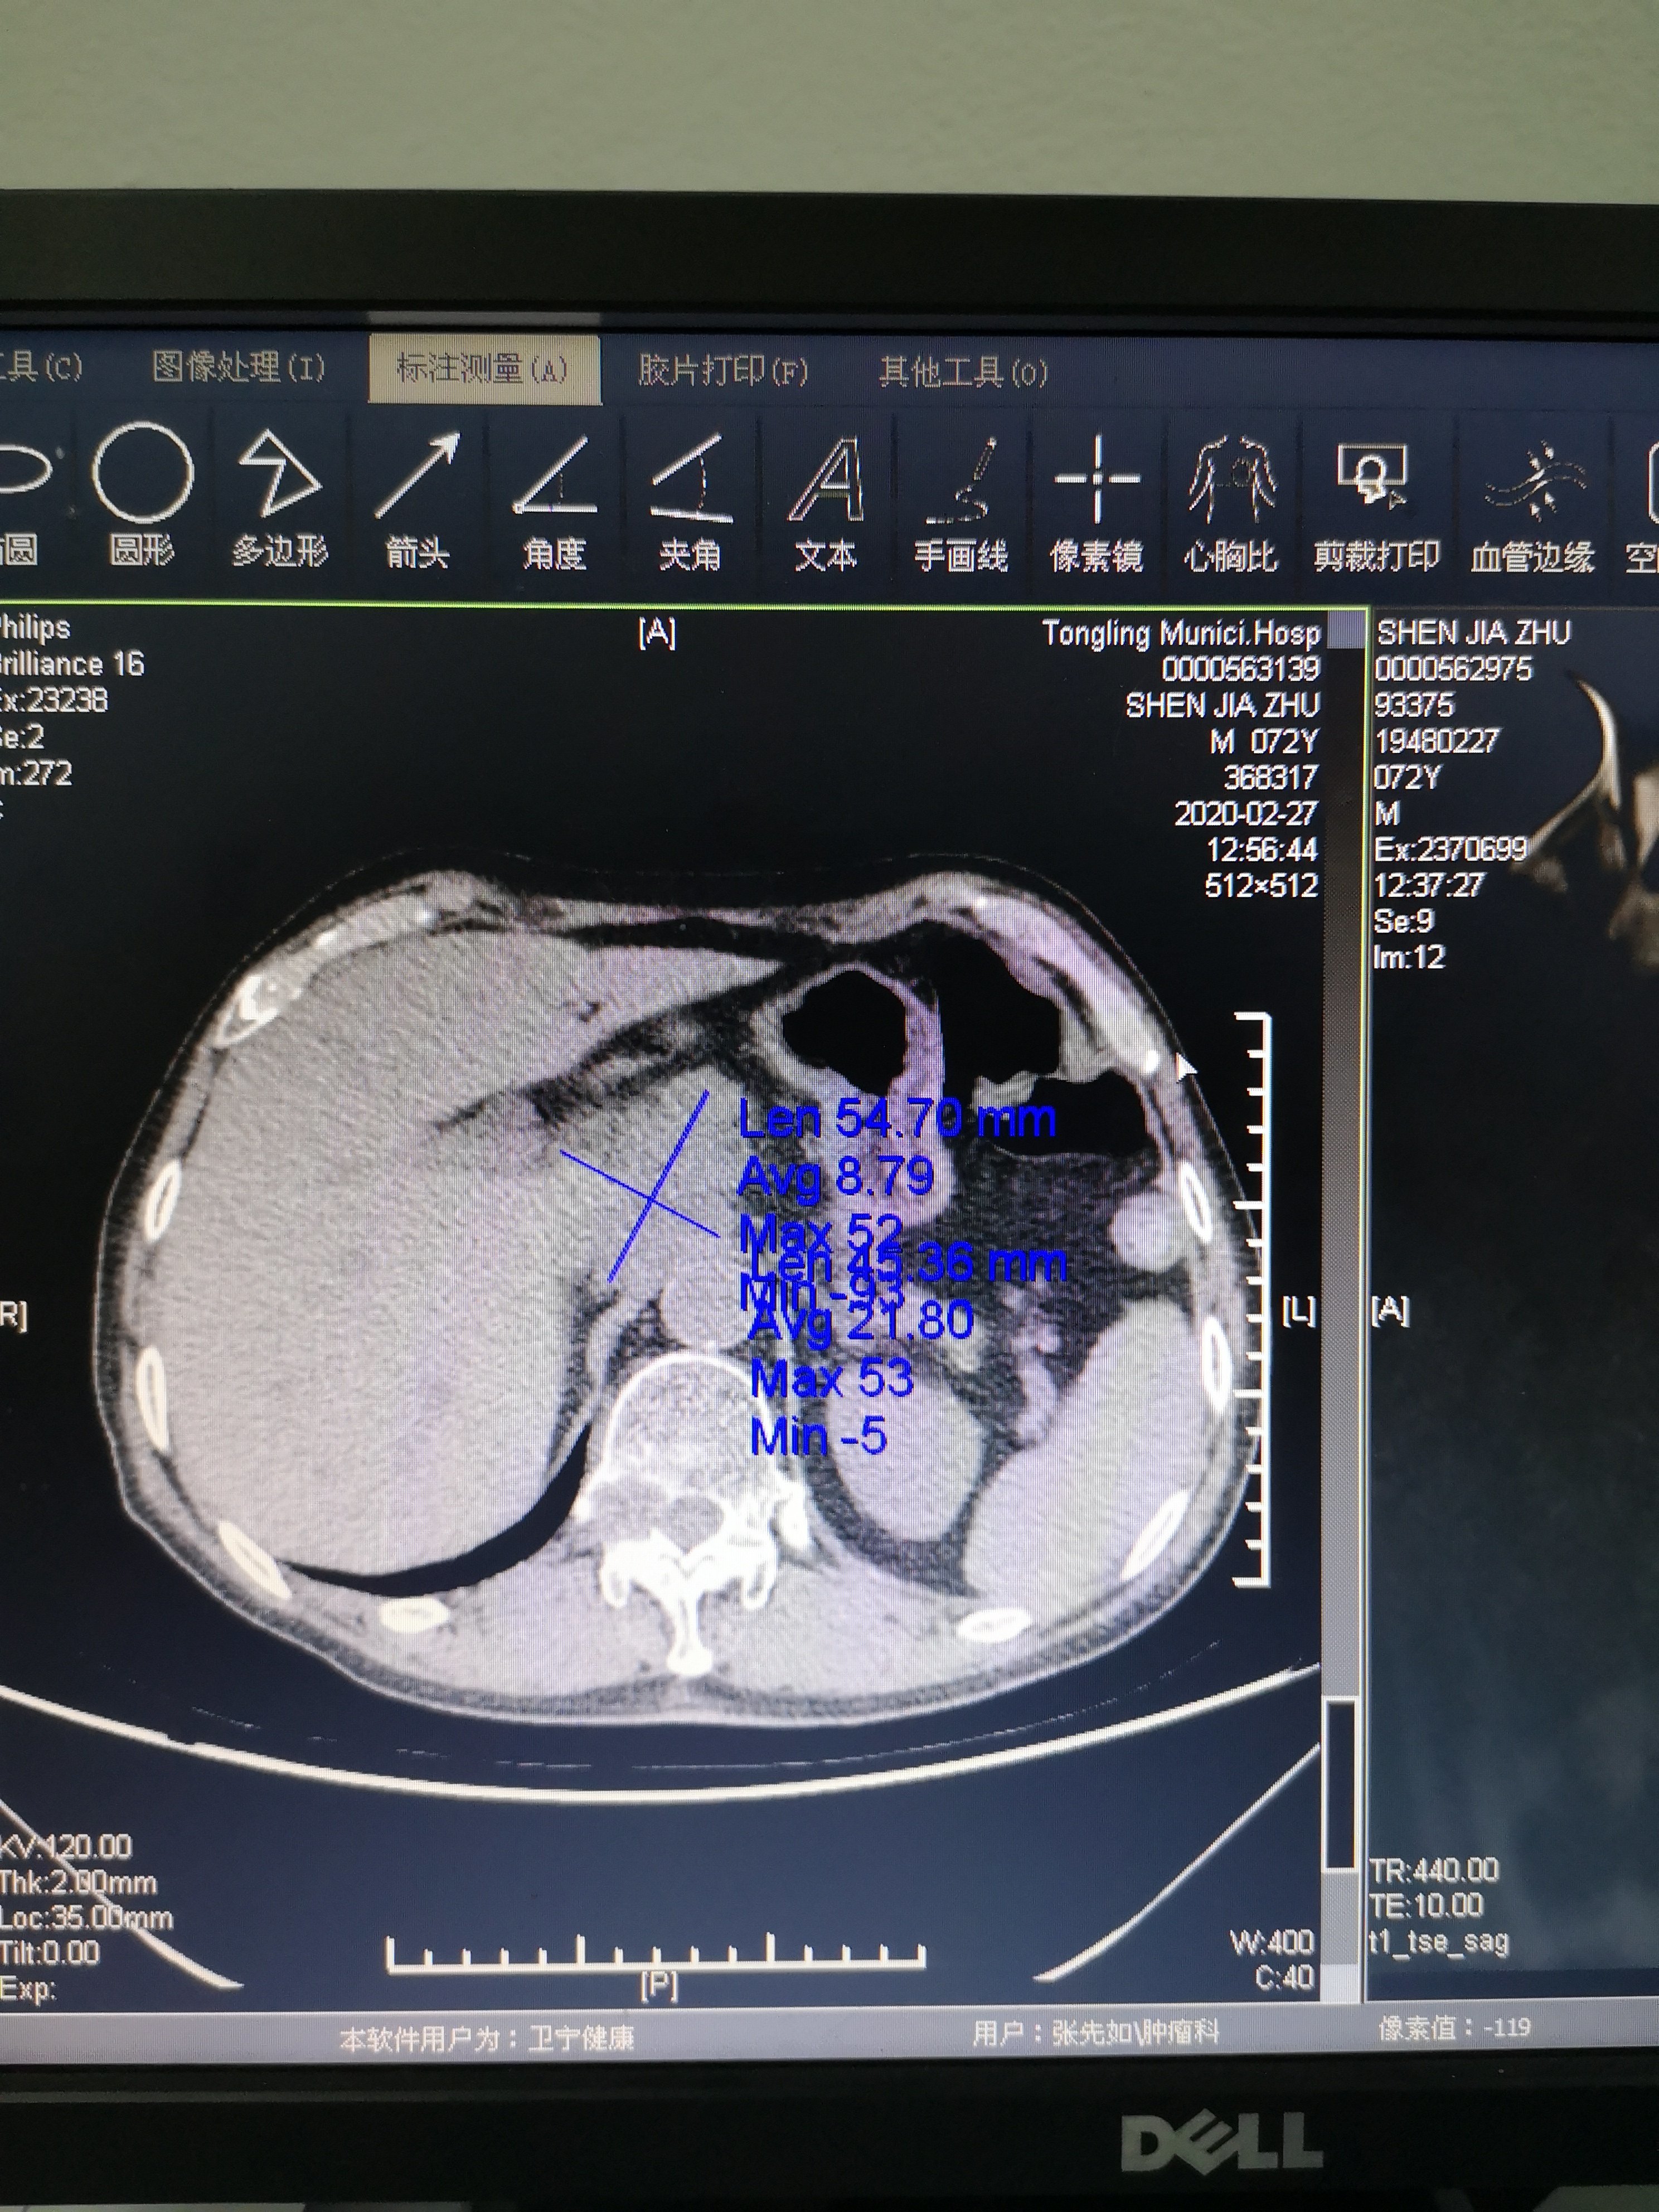

再往下看看到他腹膜后胰头处淋巴结融合团块,就是我上面标注的地方,这说明他的腹腔淋巴结也转移了!好,我们继续往下看!

从这张图上看我们可以看到左侧上面的方框内是腹腔转移,下面的小方框就是我刚才看到的椎体转移CT片,也就是右边骨转移磁共振的对应位置!

最后总结一下这个患者目前是食管癌肺转移,腹腔转移和胸椎转移!目前这个患者腹部胀痛,腰背部也胀痛!为什么会这样很明显从上面两张图我们可以看出腹部肿块已经压迫了腹部神经,这样就导致腹部胀痛,而胸椎转移灶也压迫了胸段神经丛!导致腰背部酸痛!